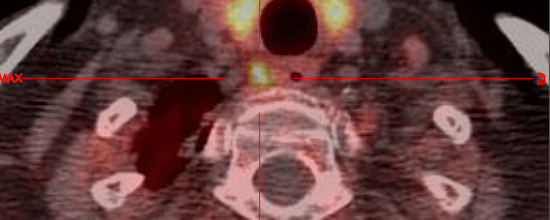

- Traitement par iode radioactif : il consiste à détruire une partie hyperactive de la thyroïde par irradiation interne.

- Dans un deuxième temps un traitement par iode 131 en comprimé appelé IRAthérapie peut compéter le traitement des cancers papillaires et folliculaires.